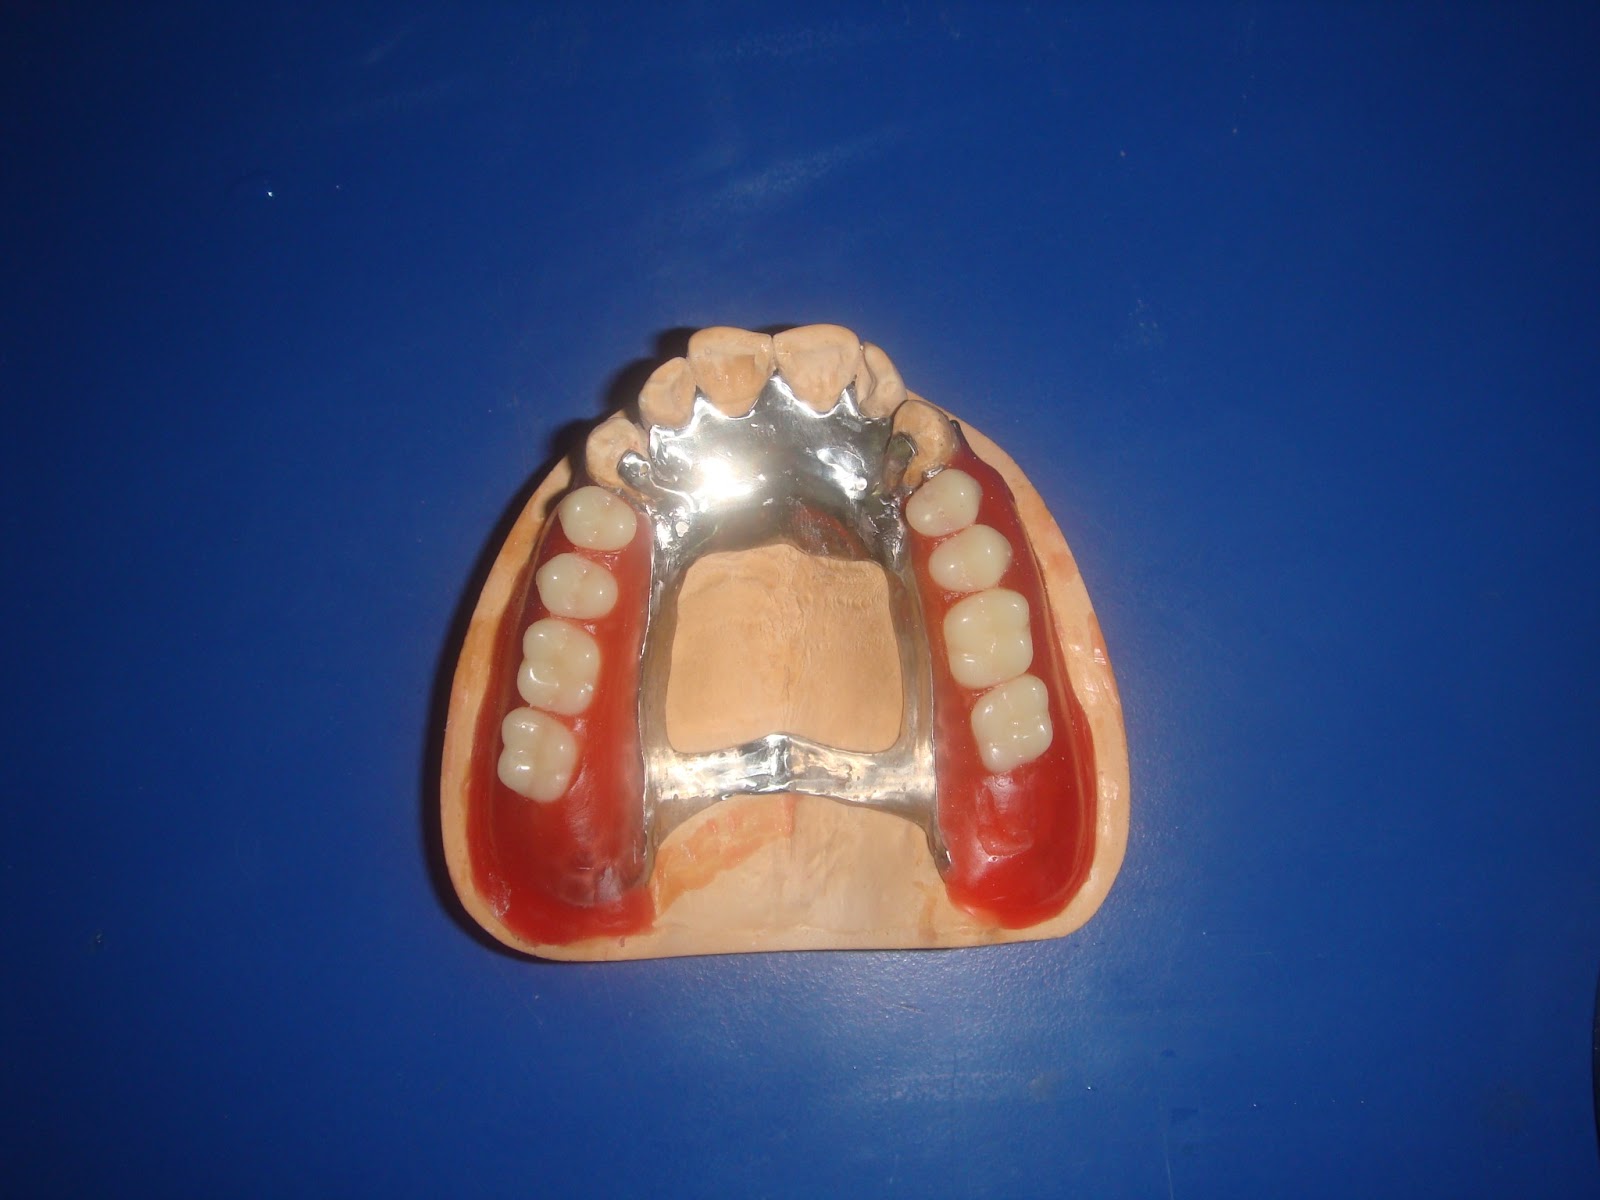

Cast Partial Denture Procedure . Cast metal partial dentures are the most common type of removable partial dentures. A partial denture that can be removed and replaced in the mouth by the patient. The removable partial dentures fabrication consists of six visits. Esthetics, mastication, occlusal support and convenience. You can take the partial denture out yourself, for cleaning and at. Partial dentures are made up of one or more artificial teeth held in place by clasps that fit onto nearby natural teeth. Preliminary impressions, diagnostic casts, and rpd design visit 2 : What is the procedure for having a partial denture? This gives the dentist an opportunity to find out all.

The removable partial dentures fabrication consists of six visits. Cast metal partial dentures are the most common type of removable partial dentures. You can take the partial denture out yourself, for cleaning and at. What is the procedure for having a partial denture? This gives the dentist an opportunity to find out all. Partial dentures are made up of one or more artificial teeth held in place by clasps that fit onto nearby natural teeth. A partial denture that can be removed and replaced in the mouth by the patient. Preliminary impressions, diagnostic casts, and rpd design visit 2 : Esthetics, mastication, occlusal support and convenience.

Cast Partial Denture Procedure Esthetics, mastication, occlusal support and convenience. A partial denture that can be removed and replaced in the mouth by the patient. The removable partial dentures fabrication consists of six visits. Preliminary impressions, diagnostic casts, and rpd design visit 2 : Partial dentures are made up of one or more artificial teeth held in place by clasps that fit onto nearby natural teeth. Esthetics, mastication, occlusal support and convenience. You can take the partial denture out yourself, for cleaning and at. What is the procedure for having a partial denture? This gives the dentist an opportunity to find out all. Cast metal partial dentures are the most common type of removable partial dentures.